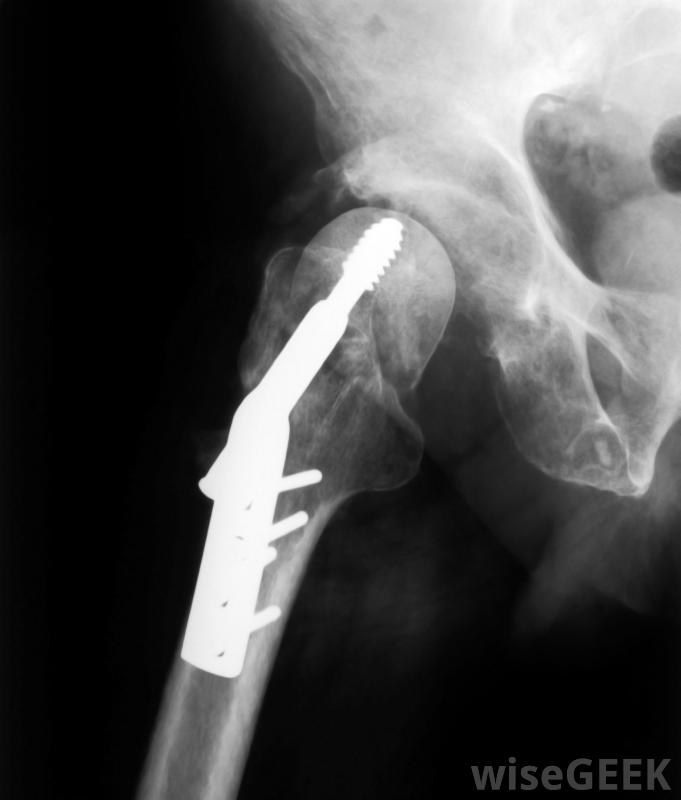

根据骨折的位置和严重程度,有时可使用动力髋螺钉固定转子骨折在骨骼的外边缘,大粗隆形成一个巨大的突起,而小粗隆在下方不远处的股骨内缘形成一个小肿块。这些骨标志意义重大,因为它们是骨骼改变方向的地方,其轴从颈部底部向下和向内倾斜,因为它们是臀部和大腿的几个肌肉的附着点,在股骨上部的解剖图中,通常包括一条被称为转子间线的假想线,它将股骨头和股骨颈平分,形成大转子和小转子之间的中点股骨骨折后恢复的个体可能需要重新建立平衡能力。转子间骨折是一种叫做转子间骨折的骨折骨折是一种骨折发生在垂直于转子间线的骨折。它表现为两个粗隆之间的裂缝,可能是部分或完全的。治疗股骨粗隆间骨折通常需要手术

股骨上部的断裂称为转子骨折。转子下骨折是转子下骨折的另一种类型。这种骨折的发生方向与转子间骨折相同,但低于或低于转子间骨折股骨粗隆。股骨粗隆骨折同样严重,需要手术修复。